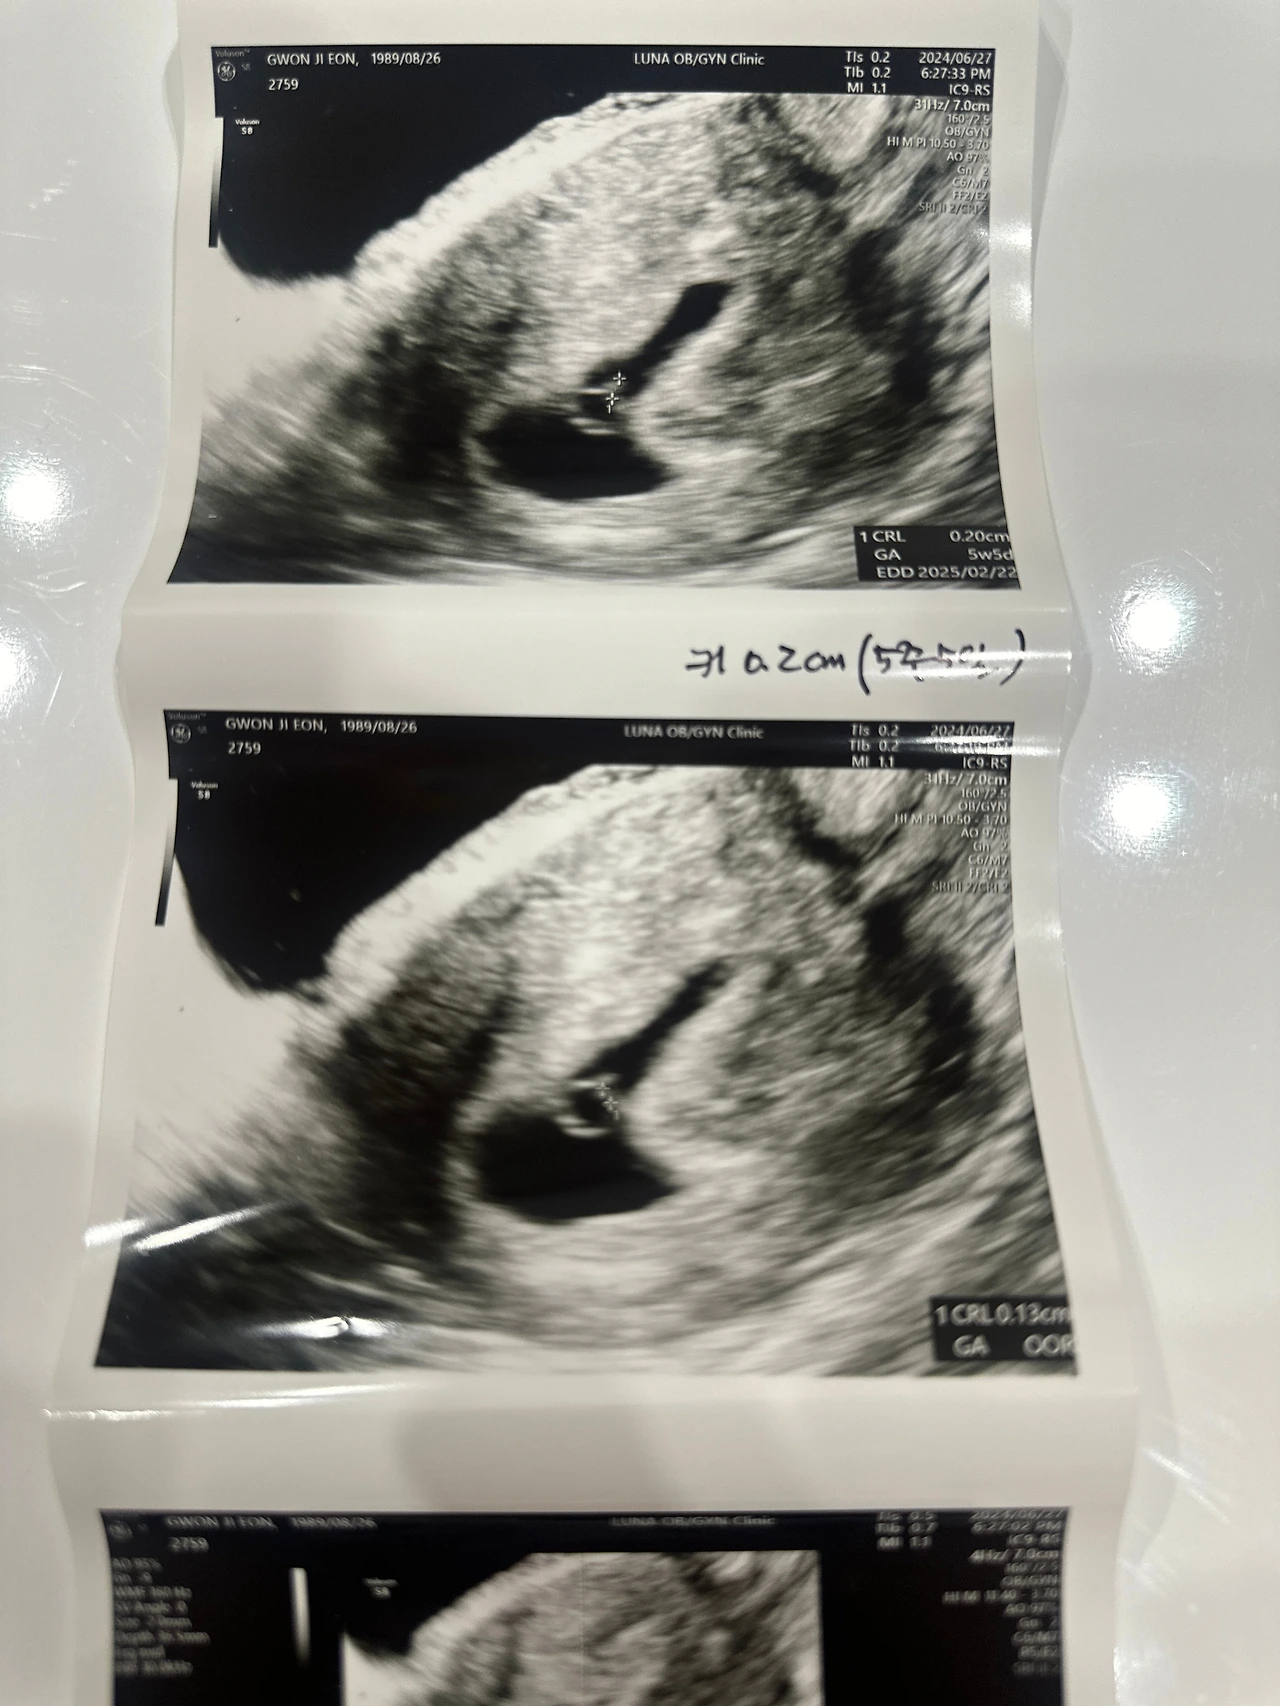

기적처럼 찾아온 아이

결혼 3년 차, 예상치 못하게 아이가 찾아왔다.

늘 불가능할 것만 같았던 순간에, 기적처럼 찾아온 생명.